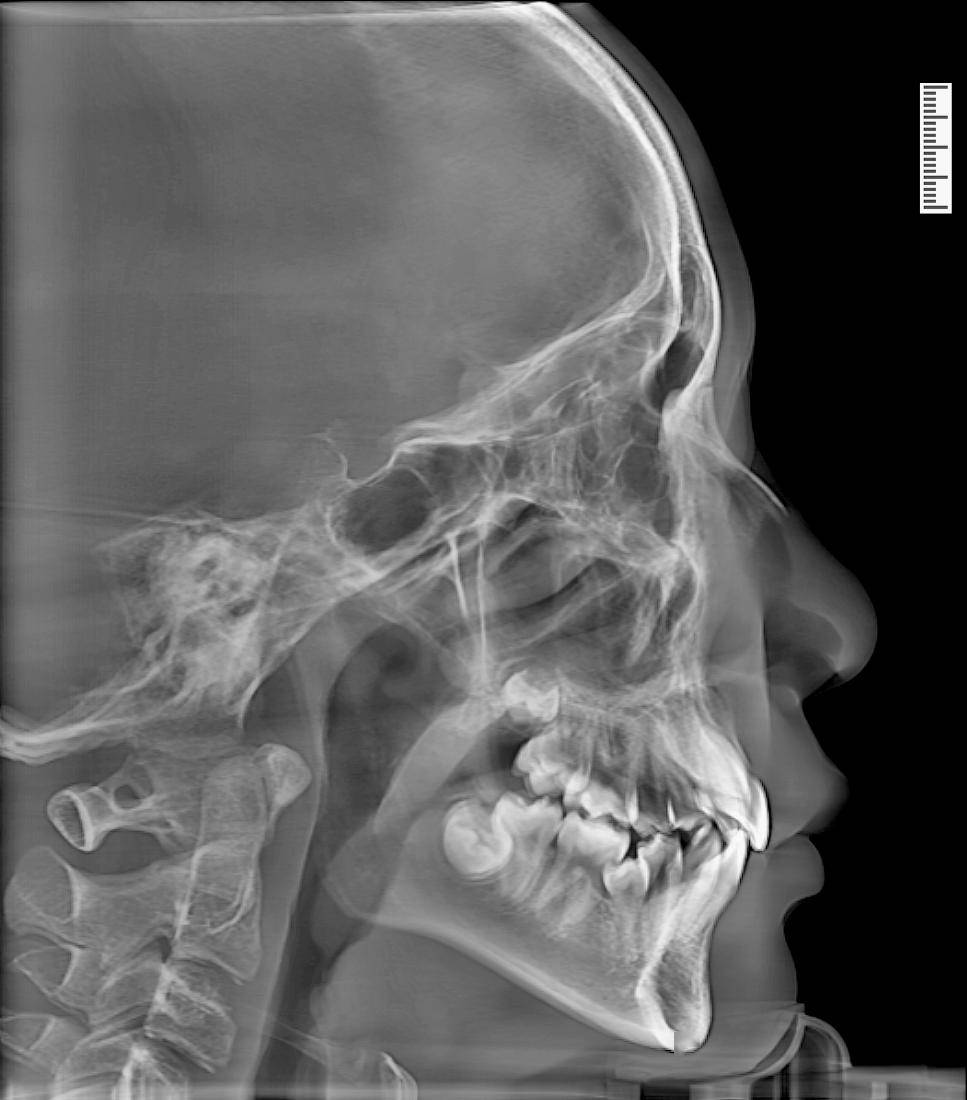

图22治疗后头颅侧位片,显示覆19覆盖正常,牙轴位置正常图23治疗后头

在评价面部矢状向位置关系时,主要使用的就是头颅侧位片,分析其中患者

正畸前后的头颅侧位片对比侧面轮廓上重要的关键点,在理想情况下,都会

正畸医生主要通过头颅定位片来观察颅骨,颌骨的长,宽,高发育情况,并

其实,正常的看诊流程中,患者需要拍个头颅侧位x线片,以供医生测量sna